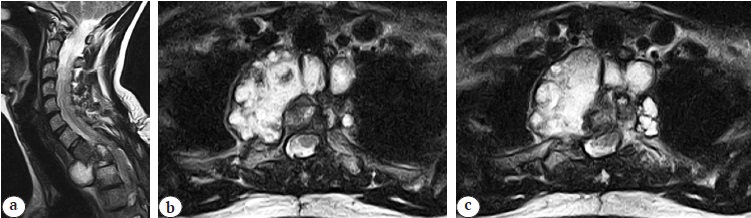

Radiological examination (multispiral computed tomography [MSCT] and MRI) revealed total Th1 body destruction, pre- and paravertebral, epidural cystic formations, and postlaminectomy cervicothoracic kyphosis of the spine of 56° according to Cobb. The nature of destructive changes and cystic formations was regarded as spinal echinococcosis recurrence (Fig. 1, 2).

Fig. 2. MRI images at the time of hospital admission: a — sagittal view: paravertebral and epidural cystic components, compression myelopathy Th1-3 level; b, c — axial view: polycystic component with heterogeneous structure